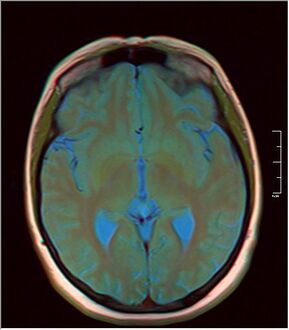

صور إضافية